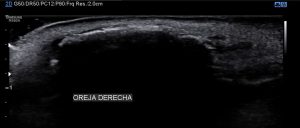

Primero es esencial saber cómo se ve esta región de forma normal.

Es una zona difícil de explorar. el acceso lo haremos mediante lineal de alta frecuencia, la más alta que podamos usar. Podemos ir por acceso anterior o por el posterior, corte en eje corto y en eje largo.

Semiológicamente veremos en la normalidad como una zona anecoica lineal correspondiente al cartílago del pabellón auricular, bordeada por tejido graso, hiperecogénico. En realidad es bastante sencillo, mira:

En el caso de este paciente, presentaba una imagen hiperecogénica que ocupaba tanto el Hélix como el ante-hélix, con una sombra acústica posterior bastante llamativa, que podía justificar la rigidez. La imagen era muy llamativa. Mira:

En la imagen 2 puede ver claramente como la anatomía está modificada, el cartílago prácticamente no se visualiza porqué está completamente calcificado. Es una imagen lineal hiperecogénica, prácticamente bajo la piel, con una sombra posterior. El corte transverso, igual aspecto de calcificación:

En esta imagen 3 puedes ver la imagen calcificada en el Hélix y el cartílago conservado en antehélix. El caso era de difícil exploración por la orografía y la colocación de la sonda, pero la imagen es muy llamativa, sobre todo correlacionada con la palpación, pero mira que con esto lo vas a entender divinamente: